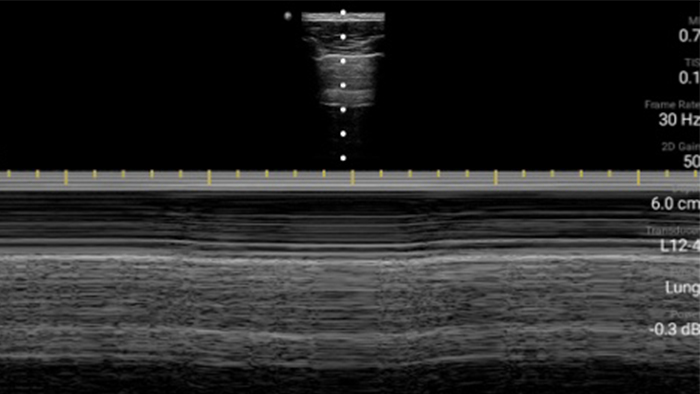

Gebruik Lumify voor luchtweg- en pulmonale beoordeling

De Lumify POCUS-oplossingen kunnen u helpen de endotracheale tube binnen de trachea te detecteren, ondersteuning te bieden bij urgente coniotomieprocedures, en diagnoses te stellen van pleurale effusie en interstitiële alveolaire ziekten.

Korte lezing

Basisprincipes van longechografie